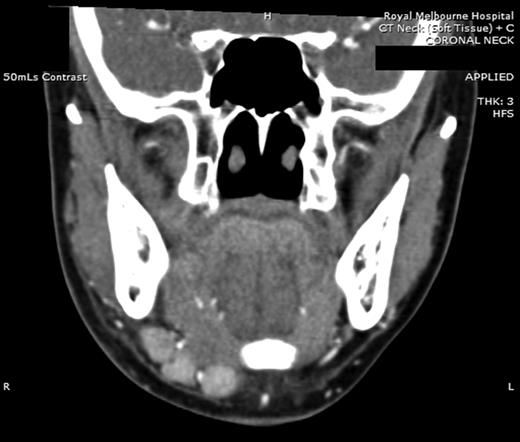

Computed tomography (CT) identified several enlarged submandibular lymph nodes (Figs 1 and 2).

Coronal CT (post contrast) showing enlarged right submandibular nodes.